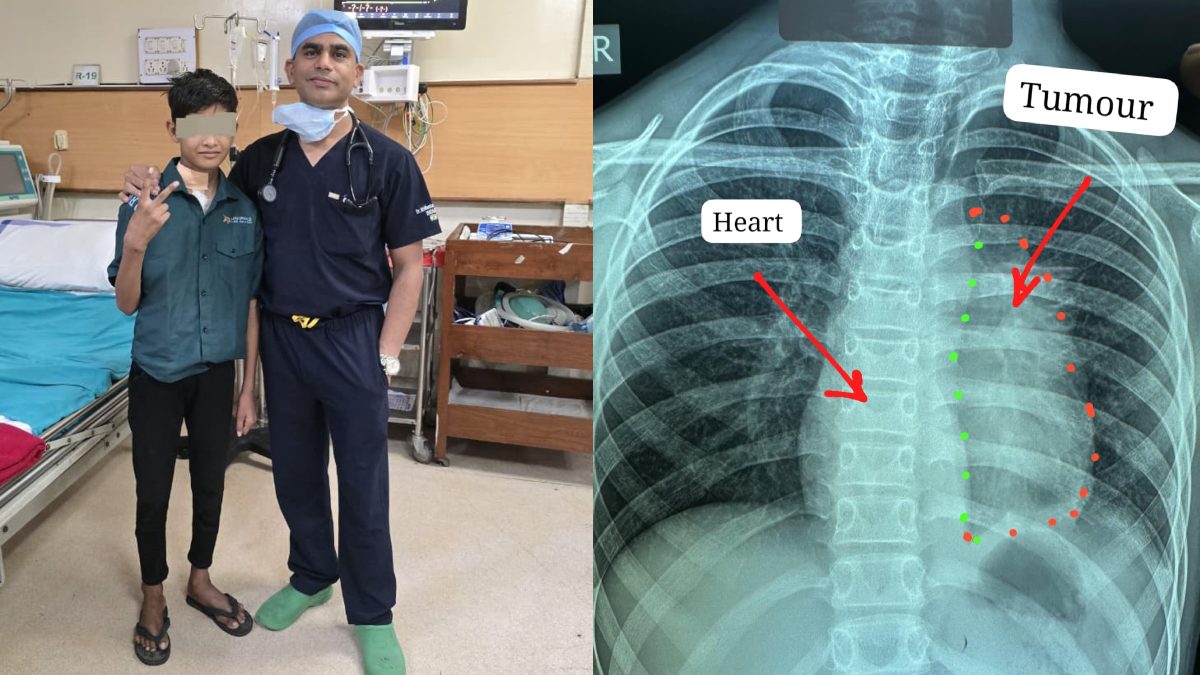

रायपुर। पं. नेहरू चिकित्सा महाविद्यालय से संबद्ध प्रदेश के सबसे बड़े शासकीय अस्पताल डॉ. भीमराव अंबेडकर स्मृति...